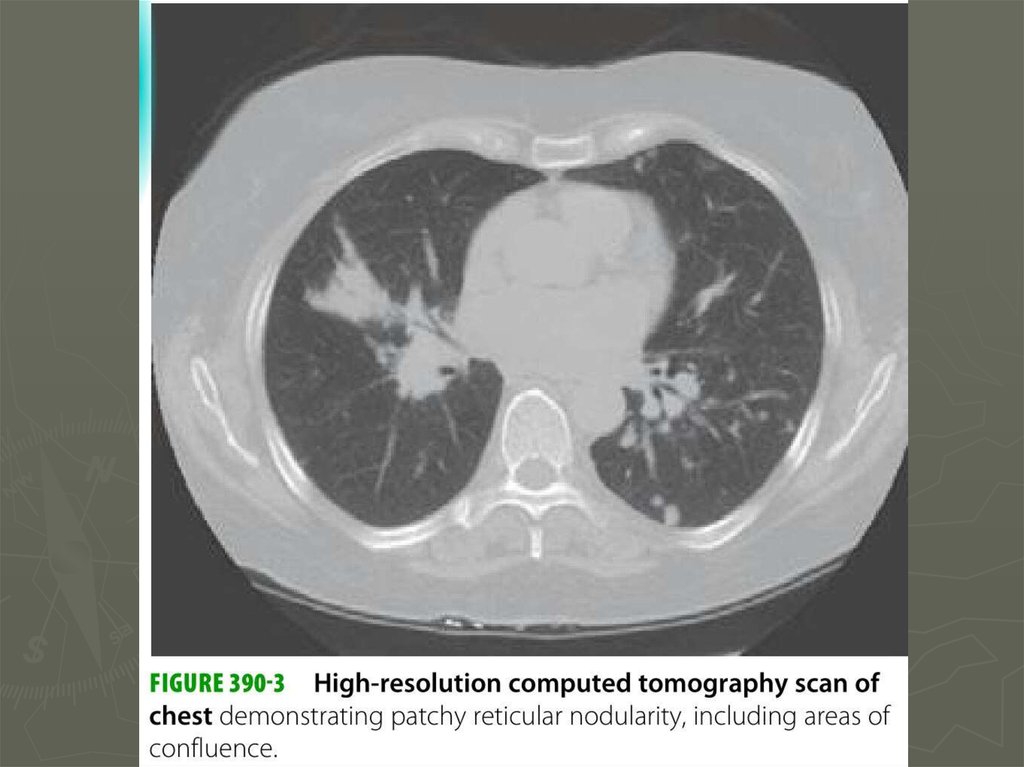

10. Диагностика

11. Диагностика